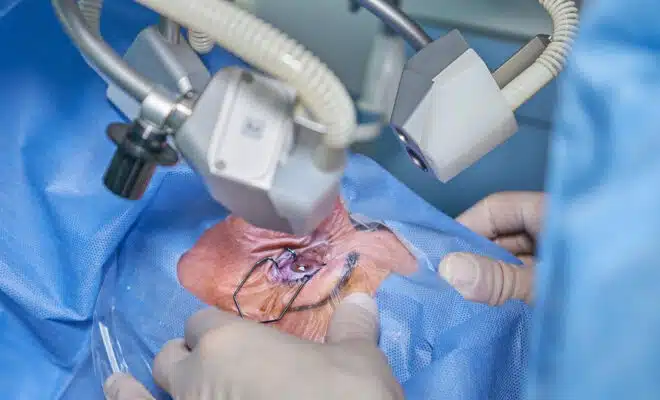

Découvrez les meilleurs remèdes de grand-mère pour consolider les os !

Suite à une chute ou un accident, vous constatez que vous avez une ostéoporose. Alors, il faut chercher un remède de grand-mère pour consolider les os. ...